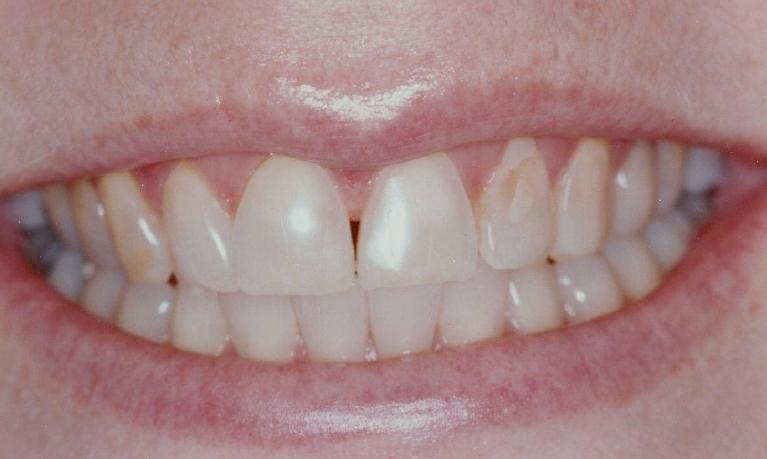

Smile Makeover with Composite Resin Veneers and Reshaping

Reshaping and composite veneer is often the most cosmetic and conservative approach to smile rehabilitation. This makeover was completed in a single visit, and no healthy tooth structure was removed.